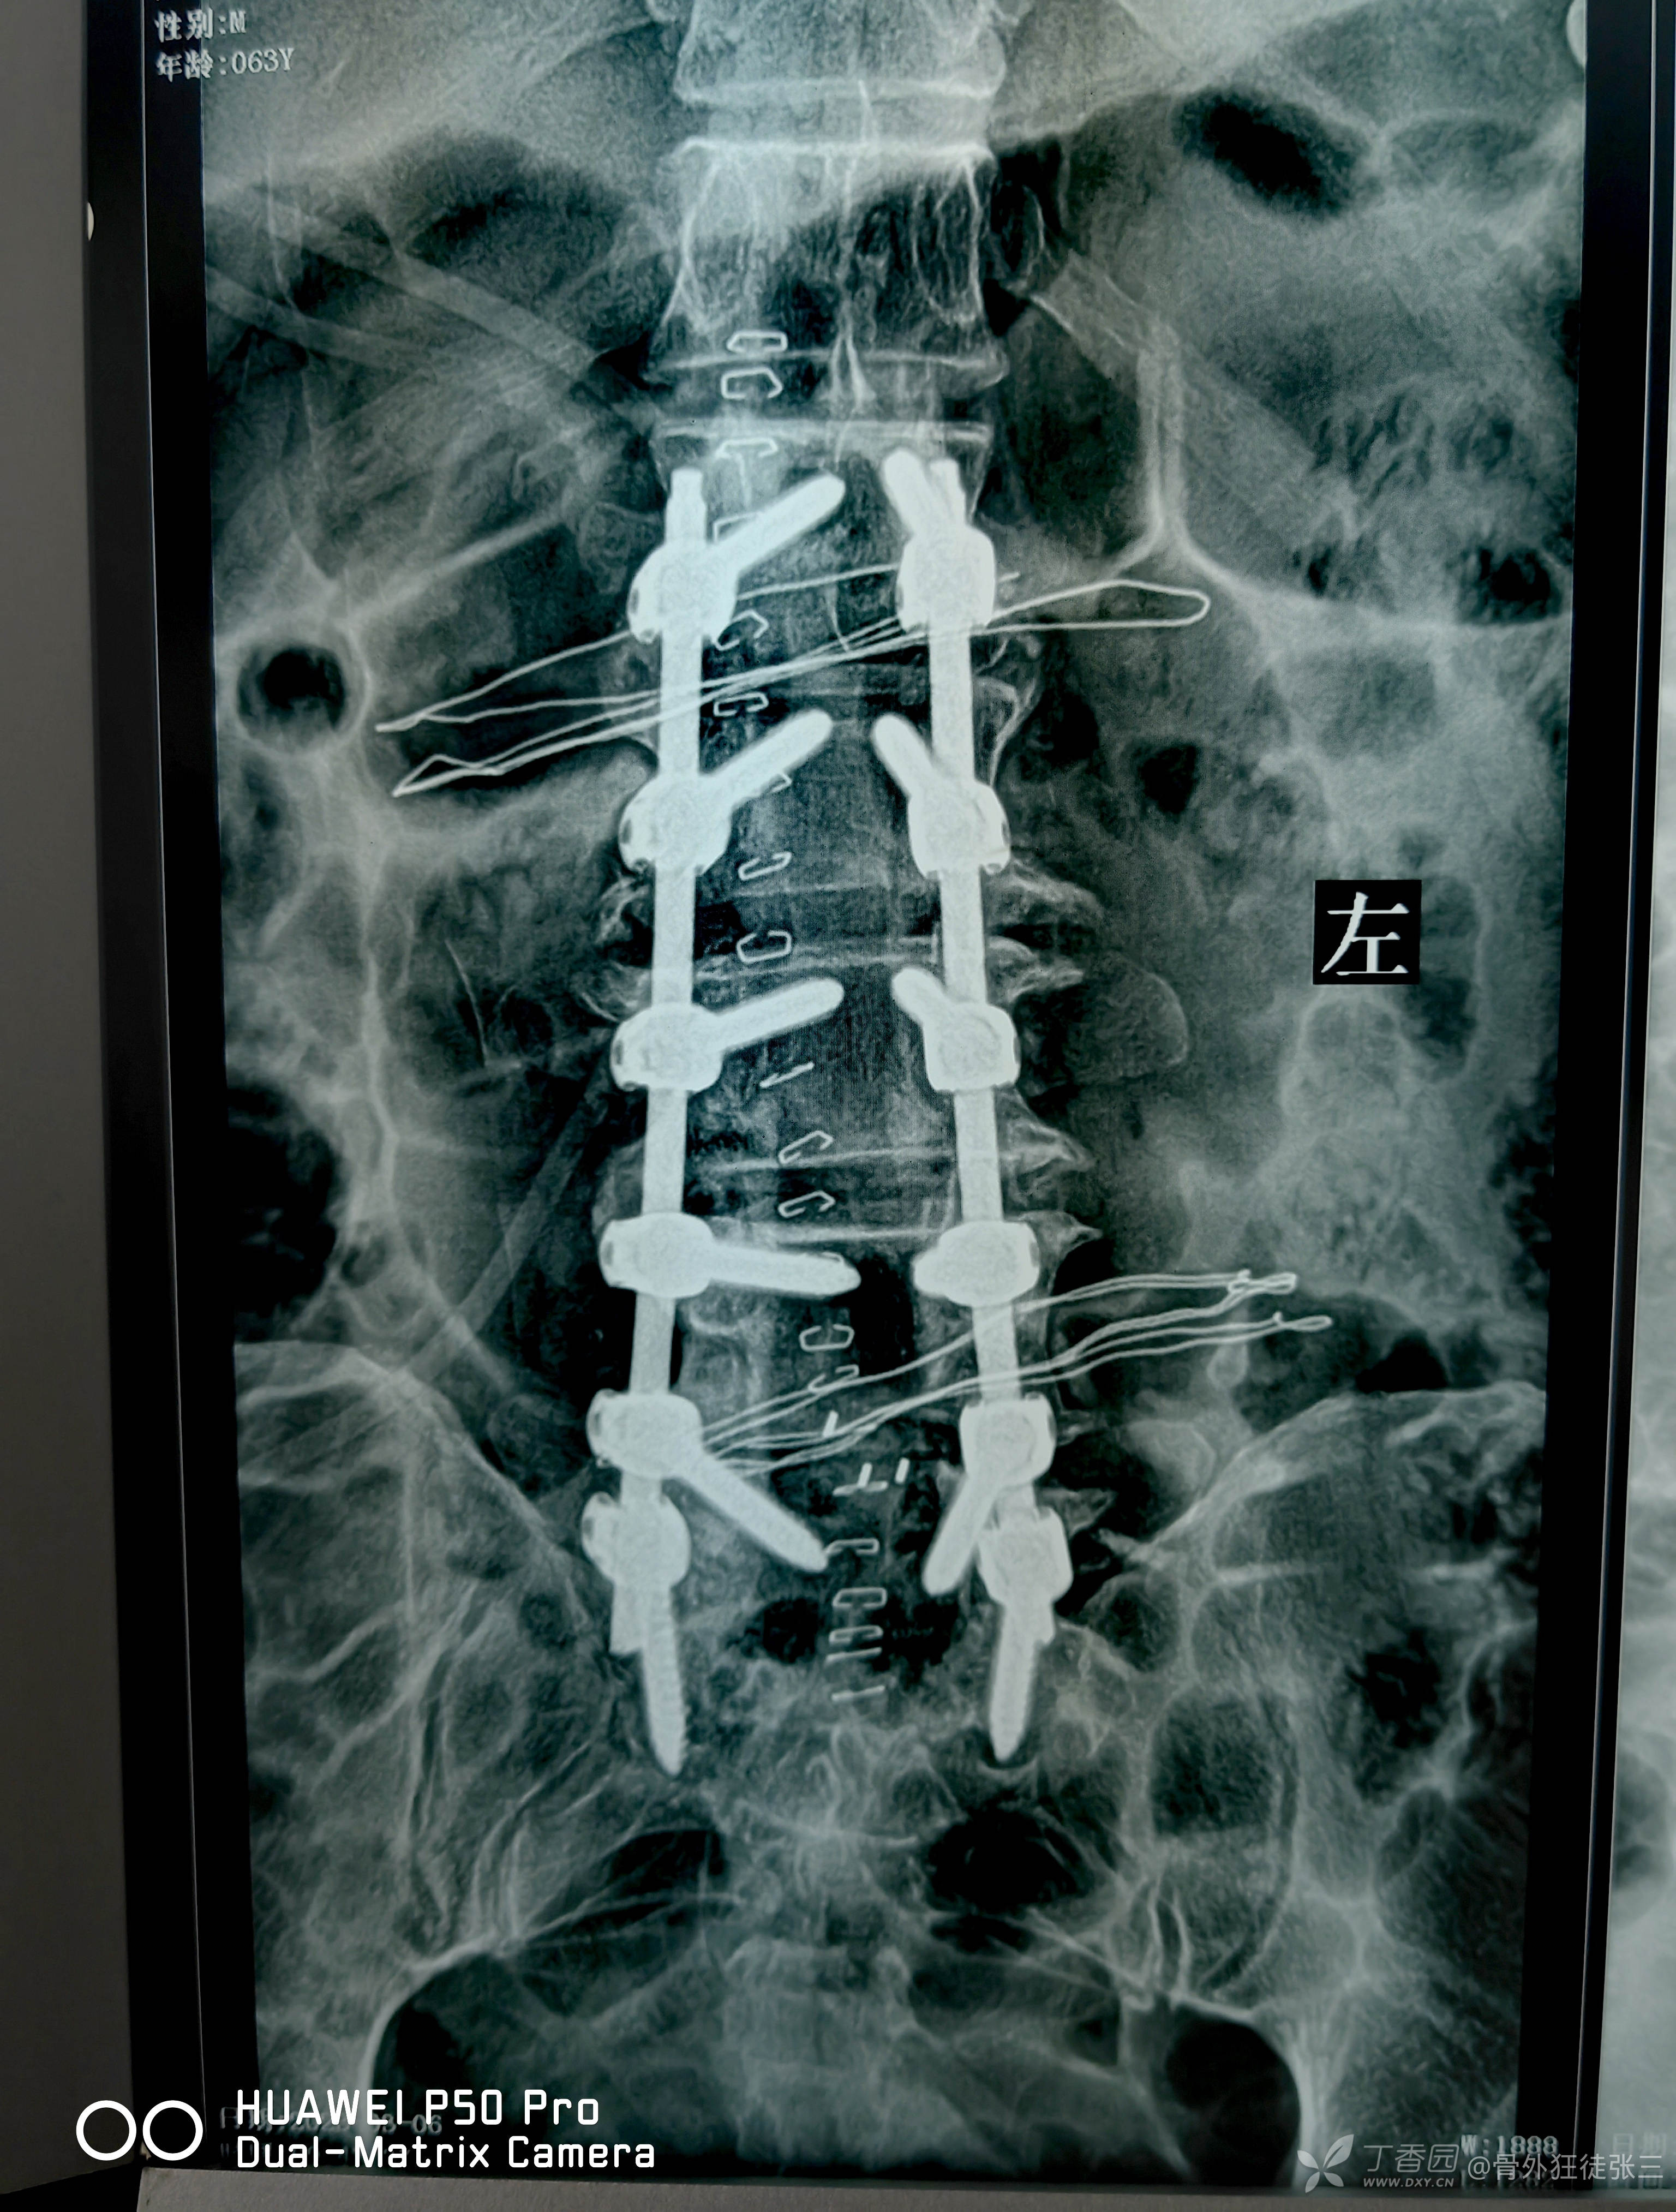

专家会诊后行手术:

L1-S1椎弓根螺钉固定,椎管扩大减压,神经根松解,L4/5,L5/S1椎间盘摘除,椎体间植骨融合术,L1/L2,L2/L3,L3/L4髓核摘除,L1-S1小关节及横突间植骨融合术。

术后第2天

我昨晚睡了一个好觉,全身轻松,也不疼了,阴囊也不麻了,掐着也有感觉了,都敢翻身侧身了,真后悔没有早点来做手术。

双下肢运动正常

会阴部,鞍区感觉恢复

腰疼,双下肢放射疼,症状消失